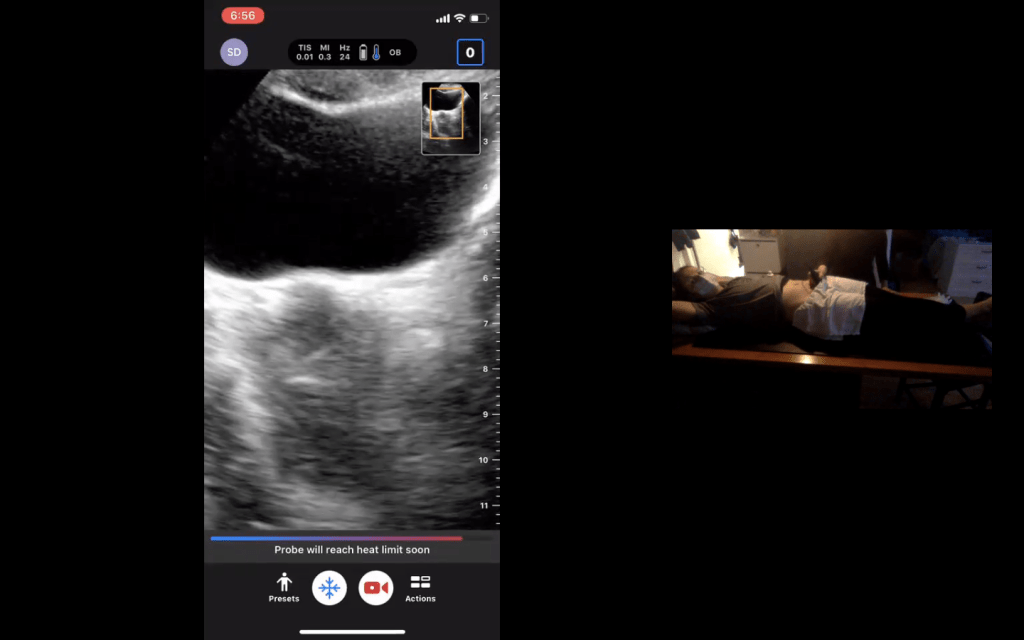

Here is a preview of our virtual session: